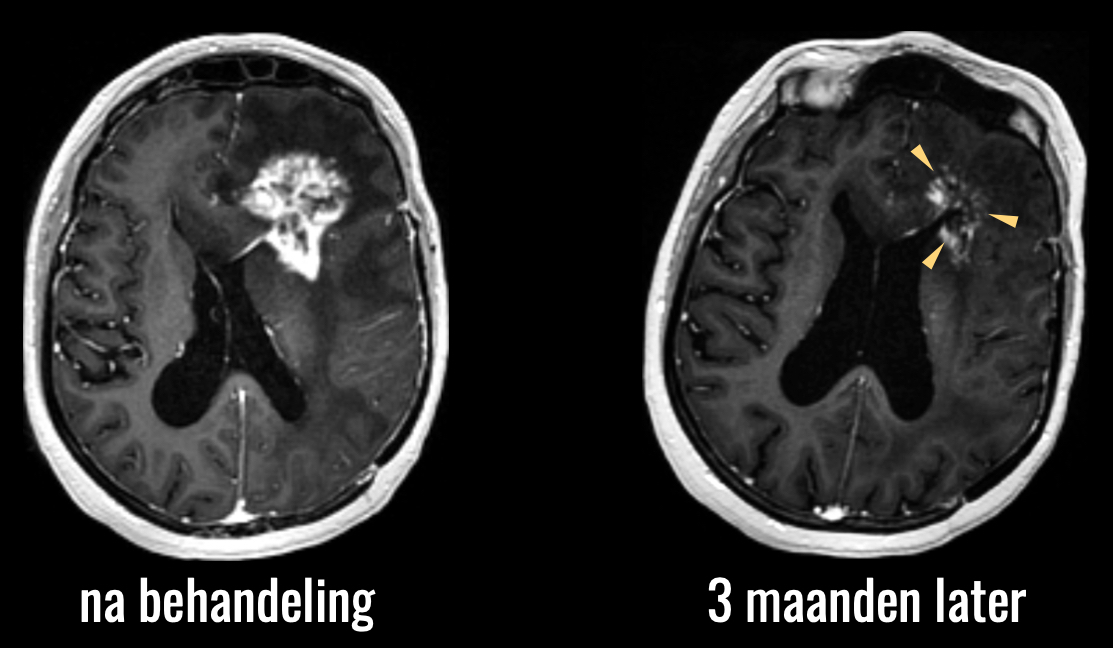

Het tweede voorbeeld betreft het omgekeerde effect, namelijk pseudoprogressie. Dit is denk ik het grootste diagnostische dilemma in de neuro-oncologische follow-up. De behandeling van een hersentumor kan namelijk leiden tot een reactie van het omringende hersenweefsel, die er op een MRI scan precies hetzelfde uitziet als de tumor zelf. U ziet hier de scan van een patiënt die behandeld is met de standaardbehandeling van bestraling en chemotherapie.

U ziet de sterke toename van afwijkingen na de behandeling.

Toename van afwijkingen na behandeling: geen onderscheid mogelijk tussen behandeleffect of toename van de tumor.

Op basis van deze beelden kunnen we niet zeker zeggen of er hier sprake is van toename van de tumor, of een reactie van het omringende hersenweefsel op de behandeling, en dus niet een toename van de tumor. Vaak is de enige optie om maar af te wachten hoe de afwijkingen zich verder ontwikkelen, met alle onzekerheid van dien, zowel bij dokter als patiënt, en natuurlijk een hoe dan ook suboptimaal beleid: als we niet weten wat er aan de hand is, kunnen we ook niet weten hoe we verder moeten handelen.

Op de scan die 3 maanden later is gemaakt, ziet u dat de afwijkingen inderdaad vanzelf weer zijn afgenomen, dus zonder dat een aanvullende behandeling nodig was.

Pseudoprogressie: eerder toegenomen afwijkingen nemen vanzelf af.